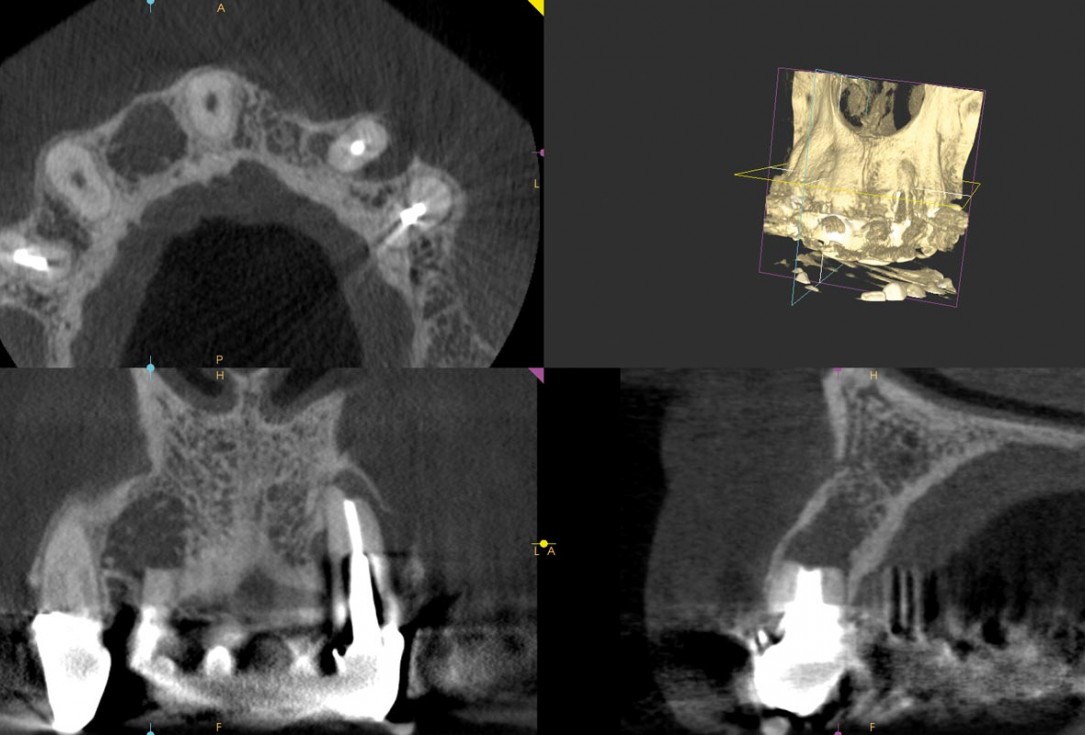

1/14 - Preoperative radiological situationAugmentation in the aesthetic zone with maxgraft® bonebuilder – PD Dr. Dr. F. Kloss

2/14 - Preoperative radiological situationAugmentation in the aesthetic zone with maxgraft® bonebuilder – PD Dr. Dr. F. Kloss